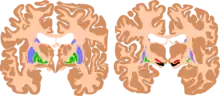

The basal ganglia are instrumental in motor function. Damage to these areas may results in athetoid/ dyskinetic cerebral palsy (ADCP), or subtle movement disorders.

CP in general is a non-progressive, neurological condition that results from brain injury and malformation occurring before cerebral development is complete.[5] ADCP is associated with injury and malformations to the extrapyramidal tracts in the basal ganglia or the cerebellum.[1] Lesions to this region principally arise via hypoxic ischemic brain injury or bilirubin encephalopathy.[1][5]

Hypoxic-ischemic brain injury is a form of cerebral hypoxia in which oxygen cannot perfuse to cells in the brain. Lesions in the putamen and thalamus caused by this type of brain injury are primary causes of ADCP and can occur during the prenatal period and shortly after.[1] Lesions that arise after this period typically occur as a result of injury or infections of the brain.[7] Cerebral cortex and white matters are often relative spared, so intelligence is often normal.

Bilirubin encephalopathy, also known as kernicterus, is the accumulation of bilirubin in the grey matter of the central nervous system. The main accumulation targets of hyperbilirubinemia are the basal ganglia, ocular movement nucleus, and acoustic nucleus of the brainstem.[1] Pathogenesis of bilirubin encephalopathy involves several factors, including the transport of bilirubin across the blood–brain barrier and into neurons.[1] Mild disruption results in left cognition impairment, while severe disruption results in ADCP.[1] Lesions caused by accumulation of bilirubin occur mainly in the global pallidus and hypothalamus.[1] Disruption of the blood–brain barrier by disease or a hypoxic ischemic injury can also contribute to an accumulation of bilirubin in the brain.[1] Bilirubin encephalopathy leading to cerebral palsy has been greatly reduced by effective monitoring and treatment for hyperbilirubinemia in preterm infants.[1] As kernicterus has decreased due to improvements in care, over the last 50 years the proportion of children developing athetoid CP has decreased.[8] In most cases, will have normal intelligence.